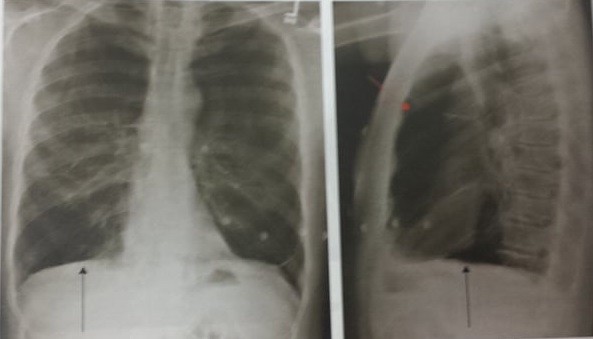

Fibroza pulmonara defineste cicatrizarea tesuturilor pulmonare. Netratată boala este la fel de agresivă precum cancerul pulmonar jumătate din pacienţi mor în primii 3 ani de la diagnostic. Durata medie de viata pentru oamenii cu fibroza chistica a crescut constant in ultimii 40 de ani. Speranta medie de viata dupa diagnosticarea fibrozei pulmonare este de aproximativ 5 ani.

Speranta medie de viata dupa diagnosticarea fibrozei pulmonare este de aproximativ 5 ani. Exista si cazuri cu evolutie marcata cand bolnavii supravietuiesc cel mult un an sau dimpotriva cazuri in care speranta de viata nu este deloc limitata. Fibroza pulmonară este o afecțiune cunoscută și sub denumirea de pneumopatie interstițială difuză fibrozantă caracterizată prin înlocuirea patologică a interstițiului pulmonar cu un țesut conjunctiv sclerozant secundar depunerii la nivel interstițial și alveolar a unor componente celulare inflamatorii fibroza pulmonară este o afecțiune mutilantă care determină în. Specialiştii apreciează însă că numărul bolnavilor nediagnosticaţi ajunge la 1000 de persoane.